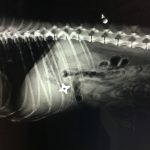

犬に関する診療実績